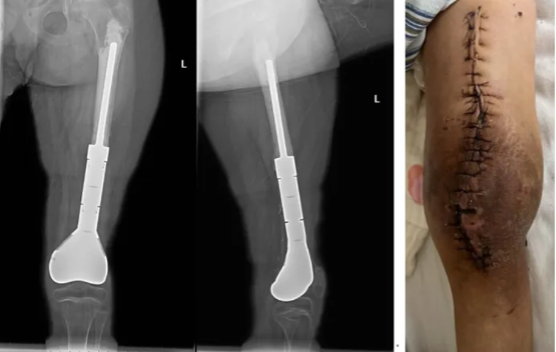

术后病理肿瘤坏死率超过95%。患者术后接受了常规辅助化疗。因肿瘤毗邻血管故采取了局部的放疗措施。

患者目前已经结疗,并在当地进行康复锻炼。

图示:患者术后复片,术后外观照